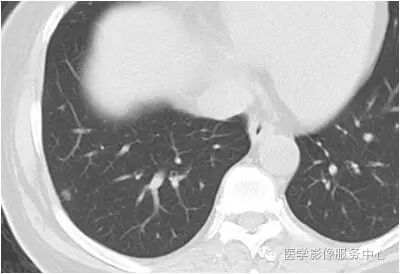

影像图片

结果:肺内淋巴结

黄勇主任解读:肺内淋巴结以老年人和吸烟者多见。

影像上常见于胸膜或叶间胸膜下,迄今为止,所有的报道均距胸膜或叶间胸膜小于2.0cm。也可以表现为与胸膜或叶间胸膜相贴的结节。绝大多数位于中下叶(气管隆突水平以下),上叶也可见到,但较少见。

长径均小于12mm。典型的形状为三角形,也可以为梭形、圆形或椭圆形。诊断的关键在于见到1-5条细线与胸膜、叶间胸膜相连,或注入肺静脉,但厚层CT显示欠佳。有作者病理对照线状影为小叶间隔,有作者病理对照为淋巴管。其实是统一的,因为淋巴管走行于小叶间隔内。

需要与小肺癌、肺转移瘤进行鉴别。肺内淋巴结除细线状影外,边缘清晰无分叶,无毛刺,是与肺癌鉴别的关键。有作者对9例胸膜下的小于1cm的肺转移瘤进行对照,后者均为圆形,且无线状影与胸膜或肺静脉相连。

对怀疑肺内淋巴结的病例,必须行薄层扫描,推荐1.5mm及以下层厚。因为在5mm层厚图像,肺内淋巴结可以由于部分容积效应表现为磨玻璃密度结节,而且对线状影及病变形状的显示也欠清晰。

诊断肺内淋巴结最关键指出在于薄层扫描见到细线状影与胸膜、叶间胸膜及肺静脉相连。